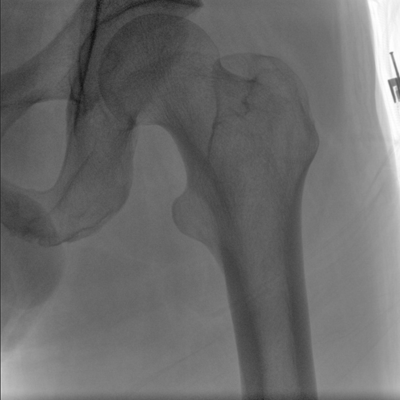

大尺寸動(dòng)態(tài)平板探測(cè)器,高DQE、低噪聲、圖像清晰。采用多分辨率圖像增強(qiáng)處理技術(shù),不同部位不同圖像處理算法,滿足客戶多樣化的需求。

采用智能變頻脈沖透視技術(shù),優(yōu)化圖像質(zhì)量的同時(shí)降低輻射劑量,呵護(hù)醫(yī)患健康